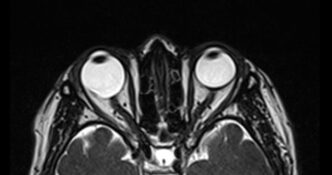

Cortes axiales de resonancia magnética de órbitas en el cual se aprecia aumento del tamaño del globo ocular derecho a expensas de su eje anteroposterior, acompañado de adelgazamiento de su pared posterior lo cual corresponde a estafiloma.

Hallazgos por imagen: Aumento del tamaño del globo ocular y adelgazamiento de sus paredes posteriores.